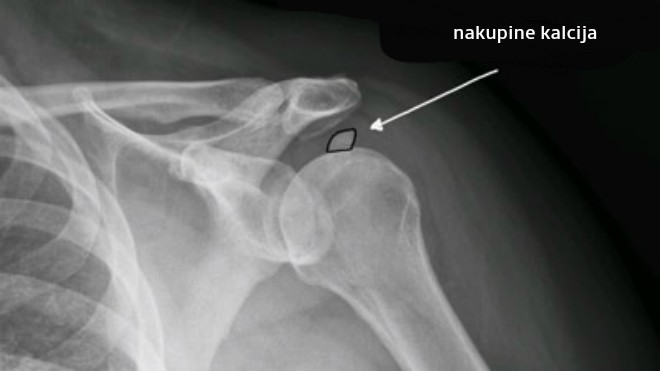

Većini ljudi kalcifikat ne uzrokuje značajne probleme te ga slučajno otkriju RTG snimkama radi nekog drugog problema. Ipak, veći kalcifikati koji uzrokuju veliku bol i smanjenu pokretljivost ruke i ramena potaći će oboljelog na posjet liječniku, koji tada upućuje na rengensko ili ultrazvučno snimanje.

Kalcifikat se stvara u tkivu ramena odnosno u rotatornoj manšeti, onom zglobu koji je zaslužan za pokretljivost i rotaciju ramenog zgloba.